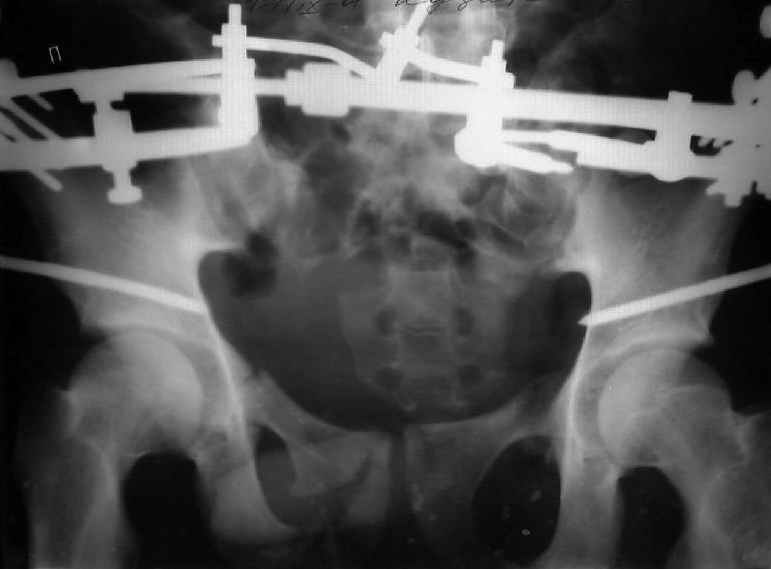

Для информации к размышлению о возможности исправления имеющейся деформации предлагаю похожий случай.